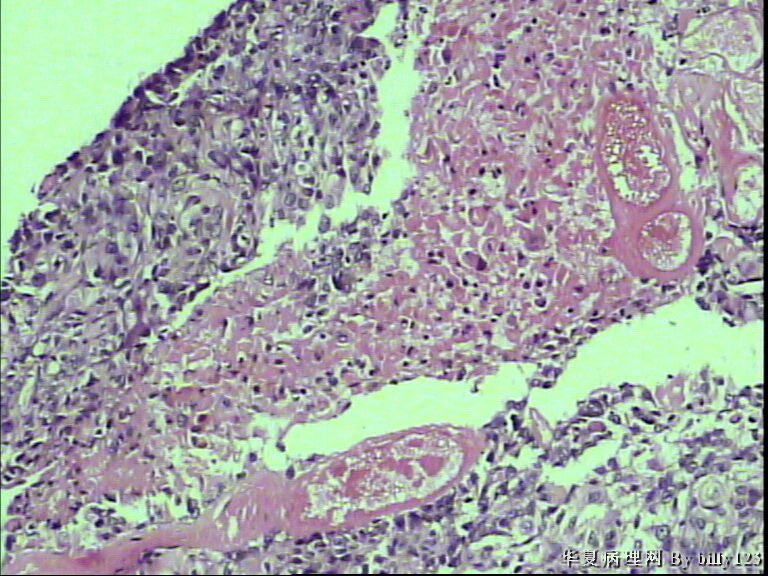

支气管活检,患者,男性,66岁,支气管镜下见息肉样新生物,鳞癌吗?请各位老师指教!

• 支气管活检,患者,男性,66岁,支气管镜下见息肉样新生物,鳞癌吗?请各位老师指教!图1

图1

从第二,三张图片的组织结构是鳞癌

全层有不典型增生 有坏死 考虑鳞癌

鳞状上皮不典型增生,炎症明显,还不能诊断癌,建议密切随访观察。